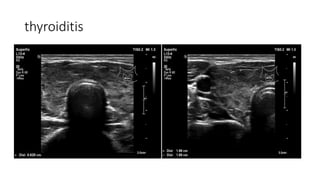

thyroiditis

Radiographic findings

• Diffusely enlarged gland with

heterogeneous echo texture

• Hypoechoic micro(1-6mm)nodules

• Hyper/normal vascularity on

Doppler

• Reactive cervical lymnodes may be

present

• #49 Heterogeneously enlarged thyroid gland with decreased color Doppler signals. hypoechoic micro nodules